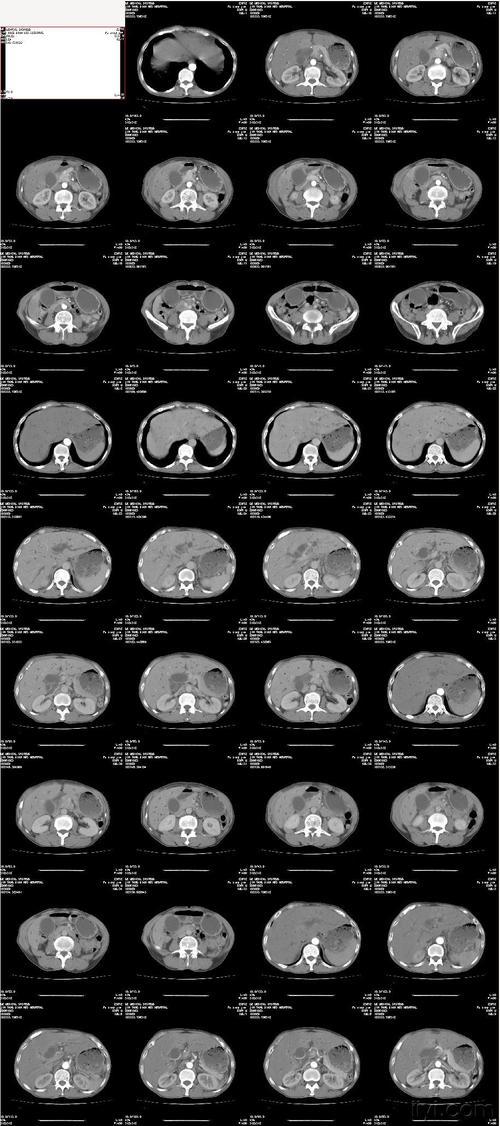

CT对于备孕期的人来说是一个比较重要的检查项目,无论CT检查量多少,都必须要做个全面的检查项目,比如说心肺听诊,肺部彩超等。如果怀孕以后,女性是拍CT过多的话,会有很大的安全隐患,还会影响到腹中宝宝的发育。

因此,如果女性是拍完CT,等到要怀孕的时候,是可以怀孕的,但是一定要注意,因为CT是有辐射的,所以怀孕以后,女性最好尽量少去到户外去,最好推迟怀孕的时间,在备孕期间,女性最好咨询一下专科医生,在这里跟专科医生的建议中也存在,在必要时尽量将身上的风险降到最低。

CT对于备孕期的女性来说是一种有益的检查方式,这种检查方式不仅有利于女性,对于男性的精子和宫内腺的观测也有一定的帮助。CT检查对于精子和卵子的发育有一定的帮助,所以女性在备孕的时候尽量不要做,如果想要怀孕,最好可以咨询一下医生,在医生的建议下做,避免在怀孕以后再做检查。